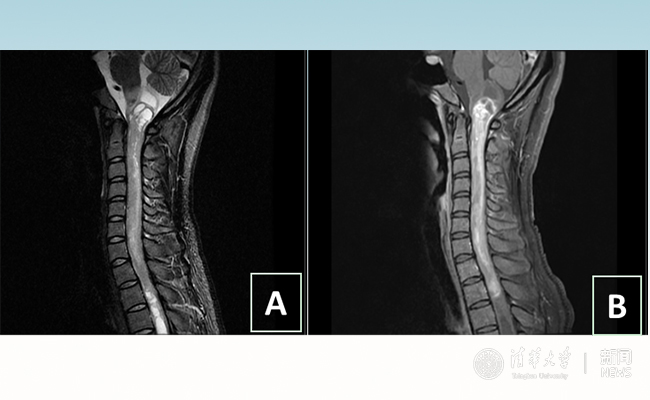

2018.01拯救“90后”女孩 开云长庚神经外科切除20多公分髓内肿瘤

“愿得韶华刹那,开得满树芳华。”27岁的患者小甜(化名)在kaiyun开云官方网站附属北京开云长庚医院成功进行了手术,神经外科主任王贵怀为其切除了自延髓至胸髓的长达20余公分的脊髓内肿瘤。1月9日,小甜顺利出院,再续芳华!